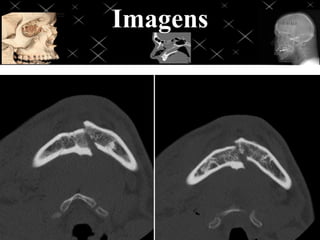

Face trauma

Aplicar os mesmos fatores técnicos e de posicionamento evidenciando a região a

ser estudada, ajustar o F.O.V de acordo com a região traumatizada, evitando

exposição desnecessária, se possível criar imagens tridimensionais para melhor

avaliação de fraturas.

OBS: para reconstruções 3D existem algoritmos

“certos” para que obtenha uma imagem 3D de

qualidade, nunca utilizar imagens com

algoritmos Bone, Lung e Edge para 3D de

visualização óssea.

Imagens